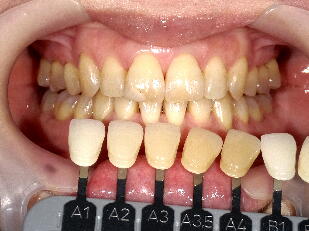

5.歯のホワイトニング ![]() ![]() ![]() ![]() ![]() ![]()

※歯のホワイトニングは期間、結果に大きな個人差があります。また歯の色が元の色に戻

っていく後戻りという現象も生じますので、詳細は歯科医師にご相談ください。